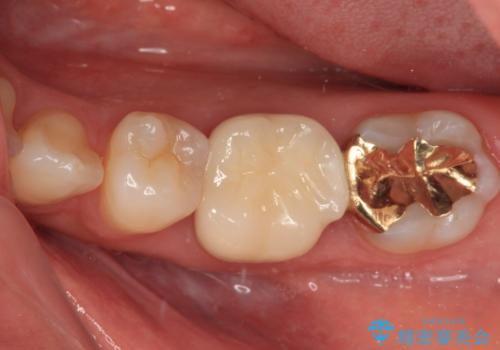

手前の歯はむし歯の範囲が広いためオールセラミッククラウンにて、最後方歯は部分的なむし歯であったのでPGAインレー(プラチナゴールドインレー)にて治療を進めることとしました。

仮詰めの状態が良くなかっただけで、むし歯が神経組織にまで及んでいることはなく、無事に治療を終えることができました。